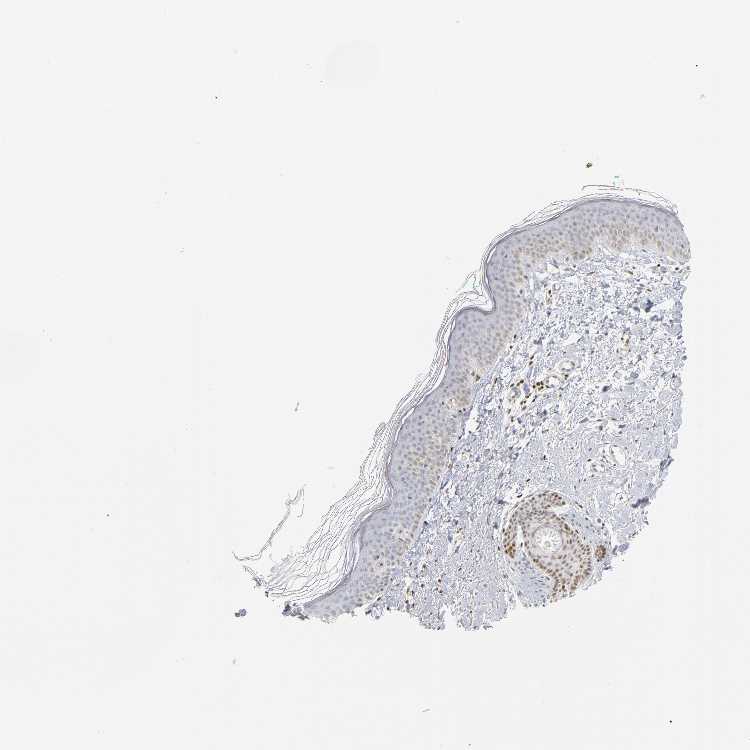

SKIN 1 - Antibody stainingi

Antibody staining in the annotated cell types in the current human tissue is reported as not detected, low, medium, or high, based on conventional immunohistochemistry profiling in selected tissues. This score is based on the combination of the staining intensity and fraction of stained cells.

Each image is clickable and will lead to virtual microscopy that enables deeper exploration of all samples and also displays staining intensity scores, fraction scores and subcellular localization as well as patient and tissue information for each sample.

Antibody HPA004176

Cells in basal layer Not detected

Cells in corneal layer Not detected

Cells in granular layer Not detected

Cells in spinous layer Not detected

Eccrine glands High

Endothelial cells Not detected

Extracellular matrix Not detected

Fibrohistiocytic cells Low

Hair follicles Medium

Langerhans cells Not detected

Lymphocytes High

Melanocytes Not detected

Vascular mural cells Not detected